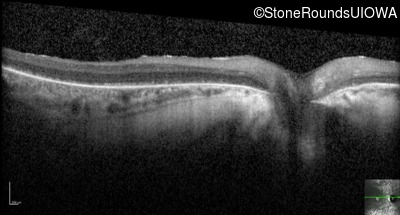

Optical Coherence Tomography - Right - 5/180

Exemplar / OCT Stack

OCT Stack